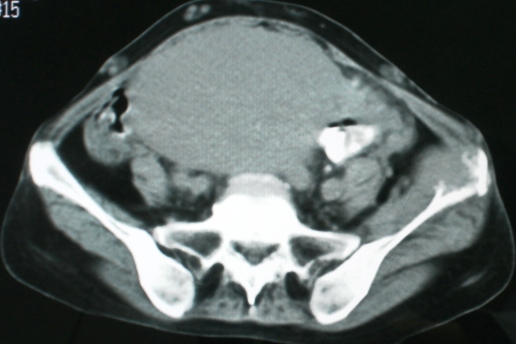

以下是引用zsl6918在2008-11-4 19:14:00的发言:[br]多发转移性改变,子宫改变不除外为原发灶